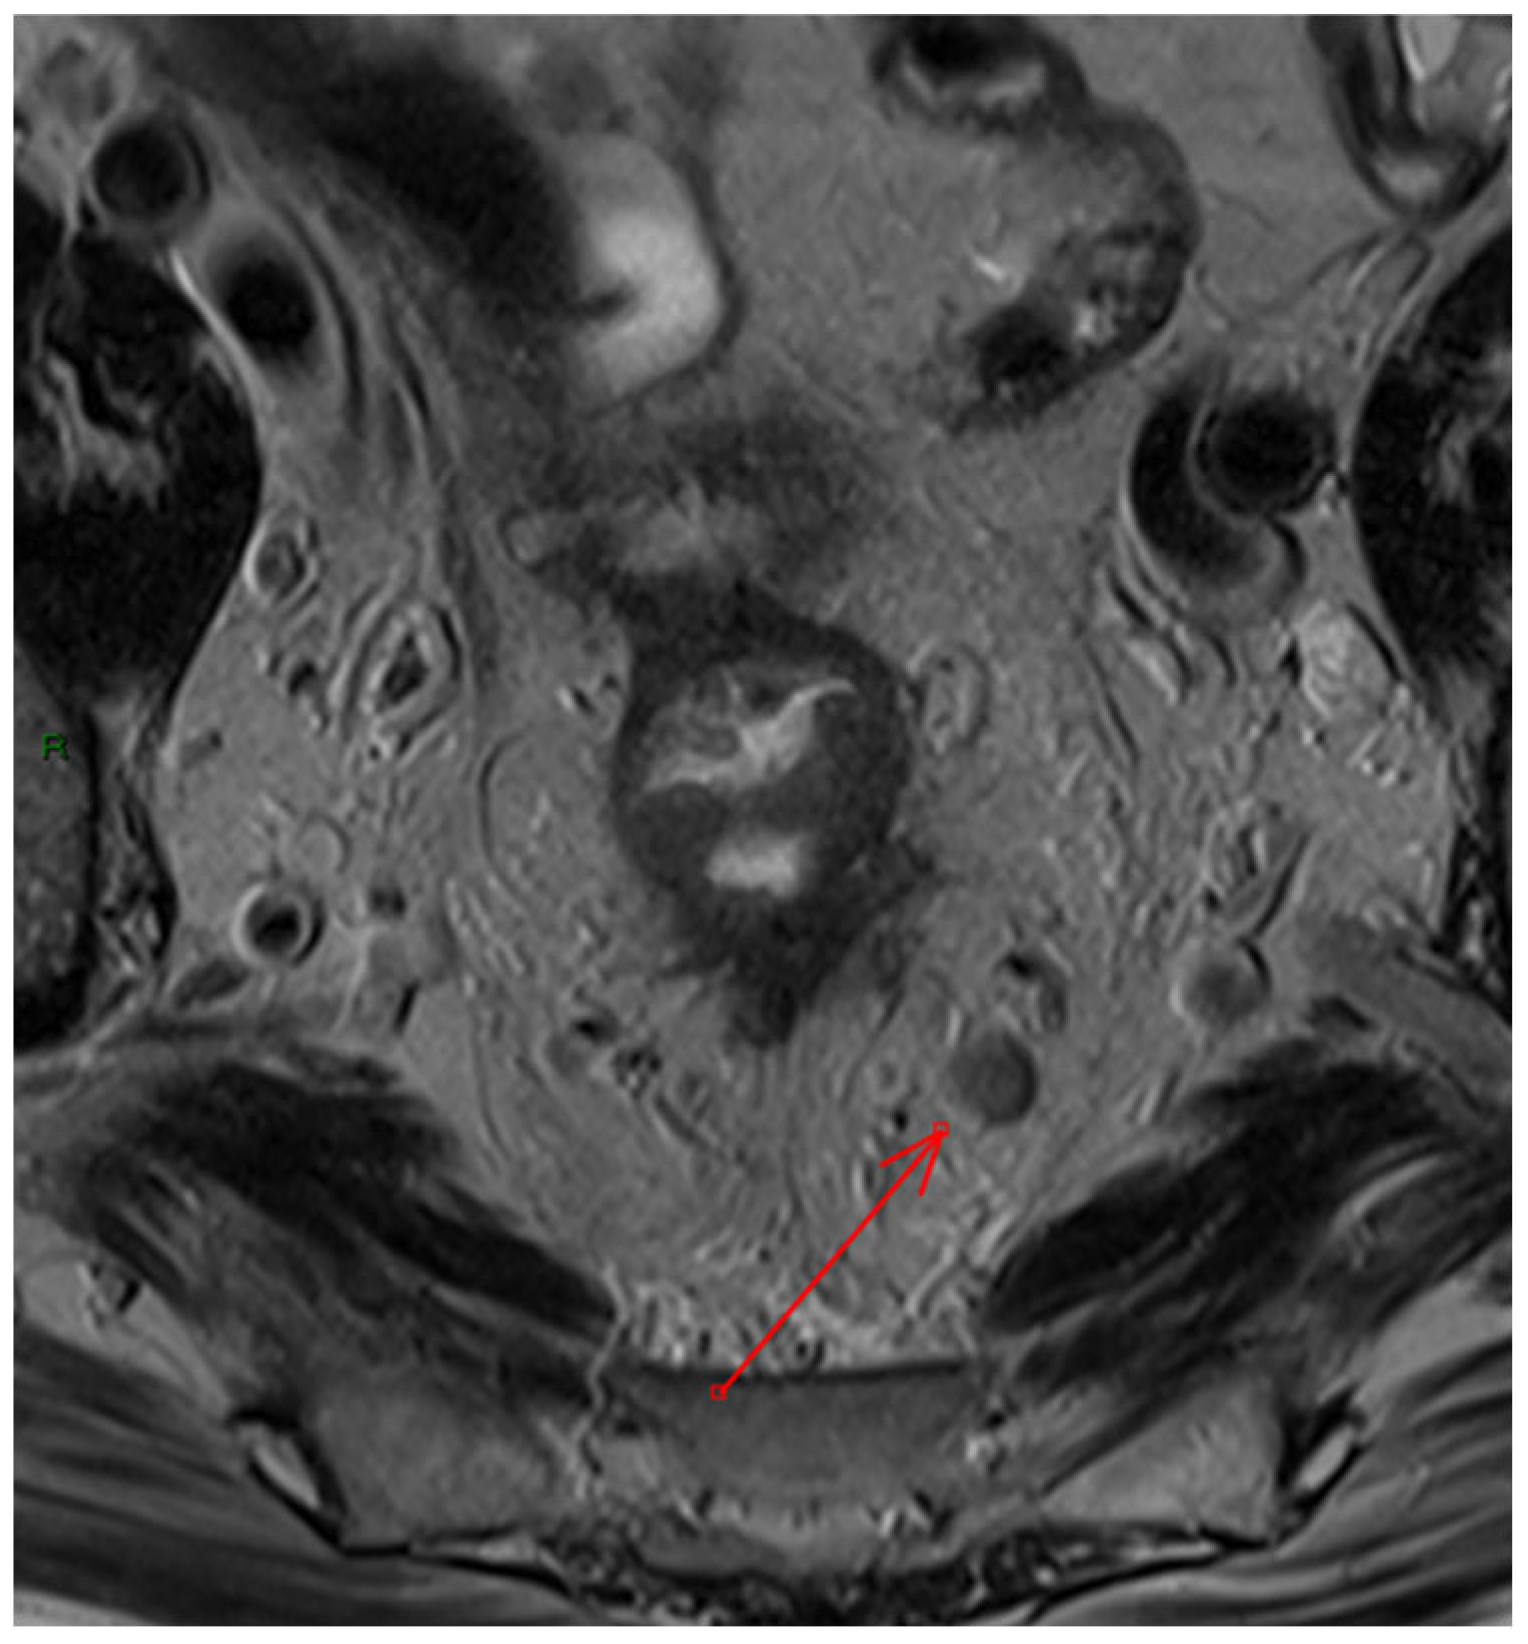

- Extramural vascular invasion as a harbinger of recurrence: The relationship between extramural vascular invasion (EMVI) and local recurrence brings to light the aggressive nature of such tumors. The presence of malignant cells in blood vessels beyond the muscularis propria near a colorectal tumor, indeed, is linked to more advanced tumors and it has been associated with a four-fold increased risk of distant metastases and a significant decrease in disease-free survival, dropping from 74% to 35% [37]. Thus, accurate histological reporting of EMVI is crucial and should be part of structured reporting.However, despite this strong association, there is still no consensus on how to tailor treatment strategies based on the positivity of this finding on MRI, and recommendations within the guidelines remain inconsistent [38,39]. EMVI is graded from 0 to 4, with grades 0–2 indicating better outcomes due to the absence of definitive vascular invasion, while grades 3–4 show vascular invasion and are linked to poorer outcomes. Furthermore, EMVI is also associated with higher TNM stage and mesorectal fascia involvement, though few studies have considered other MRI factors like tumor deposits or enlarged lateral lymph nodes, and, to the best of our knowledge, no study has investigated the variations in oncological outcomes between EMVI grades 3 and 4 [40]. The regression of EMVI following neoadjuvant treatment appears to have a positive impact on prognosis [41,42]. However, many studies evaluating EMVI regression are constrained by small sample sizes, which limits their statistical significance. Despite the prognostic significance of EMVI and the need to include it in structured reporting, further research is required to better inform treatment strategies.

- Lymph node involvement and surgical risk: Notably, our study identifies lymph node involvement as a predictive factor for postoperative bleeding. Lymph node involvement is a crucial prognostic factor in rectal cancer, making preoperative neoadjuvant therapy recommended for these patients to help lower the risk of local recurrence [11,43]. Although MRI is the gold standard for staging, it is less accurate for N staging compared to T staging, with sensitivity and specificity ranging from 58 to 77% and 62 to 74%, respectively [44,45,46]. Other imaging methods, such as computed tomography, have demonstrated similar diagnostic accuracy [47]. Our data suggest that the presence of nodal disease, which indicates a more invasive tumor, may require more delicate and extensive surgical interventions, potentially increasing the risk of bleeding. This insight should encourage surgeons to consider preoperative strategies to minimize this risk, such as advanced surgical techniques or preoperative interventions (Figure 3).